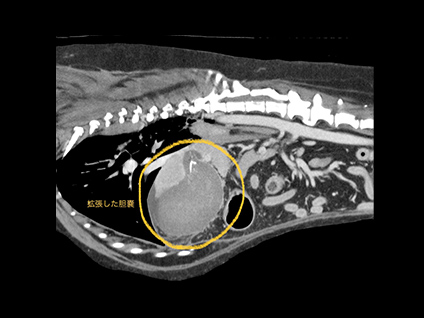

腫瘍性疾患におけるCT検査

腫瘍性疾患のCT検査は、病変の位置や浸潤、転移の有無など、手術前の検査としての役割や、抗癌剤などの治療効果判定としての役割があります。病変部やその周囲を細かく立体的にイメージできるようになるため、「より安全な手術、癌の早期発見」につなげる事ができます。